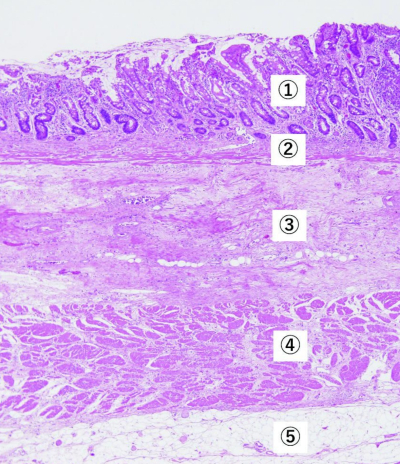

胃の正常組織の H-E 染色標本を別に示す。粘膜下層はどれか。

①粘膜層②粘膜筋板③粘膜下層 ④固有筋層⑤漿膜下層